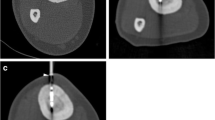

Further data sets were used to calculate the quantification of temperature changes. For this purpose, a software tool based on IDL (Interactive Data Language, Research Systems Inc., Boulder, CO) was implemented on an alternate workstation. It enables the display of temperature and tissue alterations based on SI changes derived from phase images of the GRE sequence. To further enhance visualization of SI changes during laser treatment, a color-coded subtraction method was used (Fig. 4). Direct postinterventional, contrast-enhanced (Magnevist; Bayer-Schering, Berlin, Germany) MRI was performed to confirm total ablation, typically showing loss of nidal contrast enhancement (Fig. 5) [8, 11].

MR thermometry with T1-w GRE (TE/TR 2/4.3 ms; fa 27°, acquisition time 4 s) (A) at the beginning of the laser ablation and (B) after 11 min. Note the T1 effect as a hypointensity of the ablation area, indicating qualitative temperature rating. (C, D) Display of software interface for temperature mapping demonstrating temperature and tissue alterations based on SI changes derived from phase images of the GRE sequence with a color-coded subtraction method